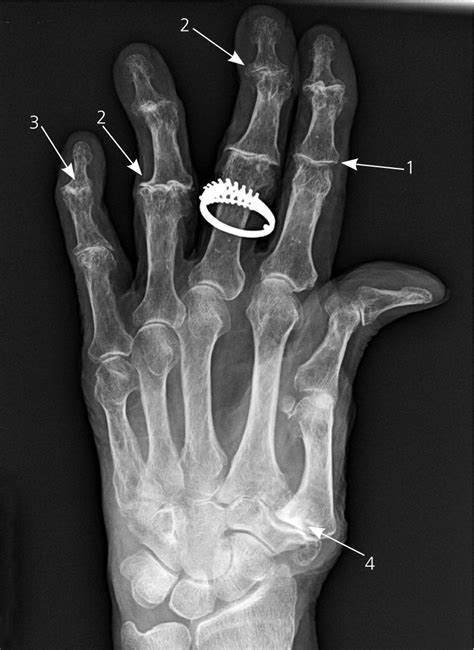

医生将询问你的症状,同时检查你的关节,还会给你拍X线片子(如下图所示),必要时可能还需要抽血。

医生将根据你的症状和临床体检以及X线检查结果等来进行诊断。

手指骨关节炎的X线